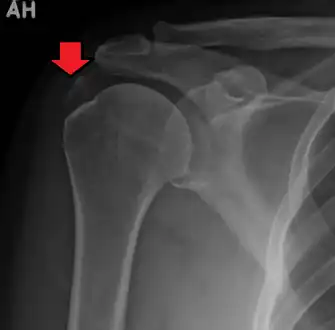

| A plain X ray of the shoulder showing calcific tendinitis | |